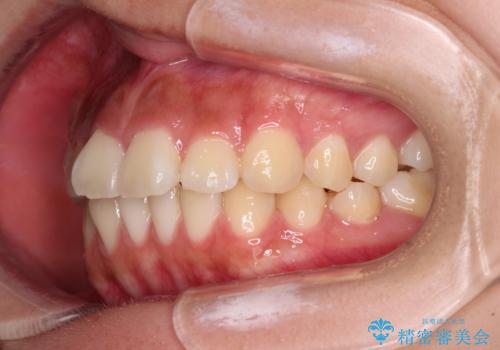

- 口元から飛び出てしまう前歯を気にして来院された患者様です。

上下前歯が嘴のように前方に突出しており、唇が閉じにくい状態であったため、上下左右の第一小臼歯4本を抜歯して、口元の突出感を改善することとしました。

目立たない装置を希望とのことで、上顎が裏側、下顎が表側のハーフリンガル装置を用いることとしました。